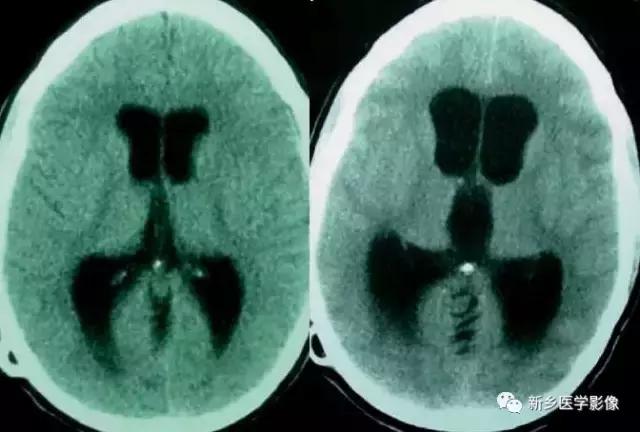

1.导水管狭窄:

中脑导水管是脑室系统最狭窄的通道,也是脑脊液循环受阻最常见的部位。

导水管狭窄的病因比较复杂、主要包括:①先天发育性狭窄②导水管周围胶样变③导水管粘连等。先天发育性狭窄可呈线样狭窄、分叉样狭窄或横膈膜形成。导水管周围胶样变多为炎症所致,主要见于宫内先天感染后,尤其是弓形体感染。

导水管粘连主要见一于颅内感染和出血后,可于胚胎期发生,也可见于出生后任何年龄。导水管粘连所致狭窄多位于导水管远端。狭窄段长度通常为2一5mm,狭窄近端异水管可呈喇叭口样扩张。

导水管狭窄时,三脑室扩大常很显著,三脑室前部视隐窝和漏斗隐窝扩张或消失,三脑室后部松果体隐窝和松果体上隐窝明显后突,向小脑上池疝入。严重者可压迫小脑。